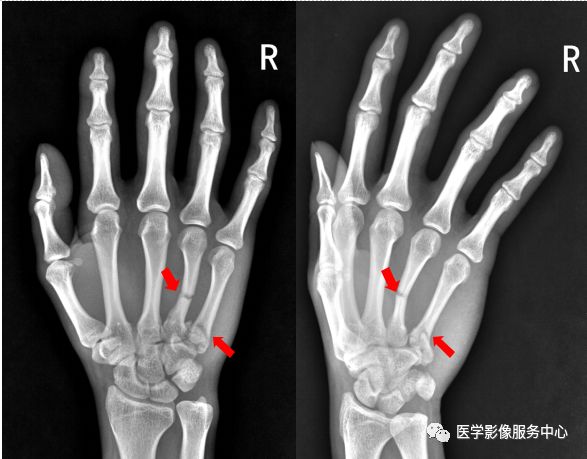

右手第五掌骨远端骨皮质不连续,骨折端移位、成角。右手第五掌骨骨折(1-5. 第1-5掌骨)

右手第四掌骨中段、第五掌骨基底部见横行骨折透亮线,骨折端对位对线尚可。第四、第五掌骨骨折。